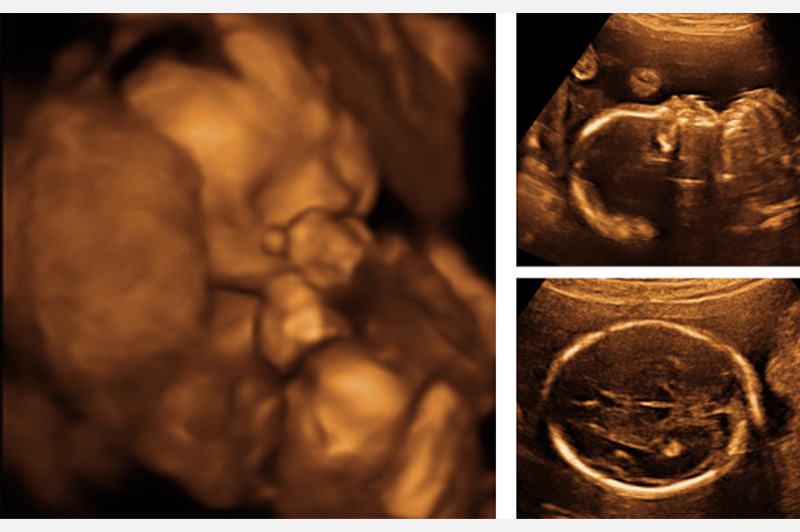

產前高層次超音波 胎兒異常先知道

奇美醫學中心 彭依婷|婦產部 主治醫師